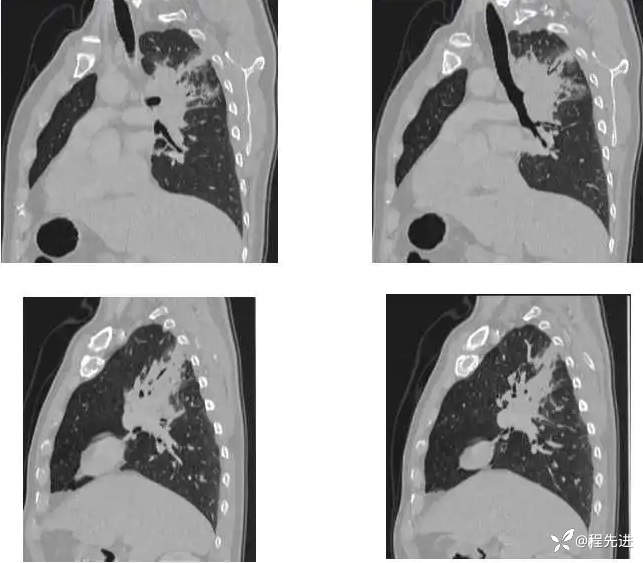

CT增强: